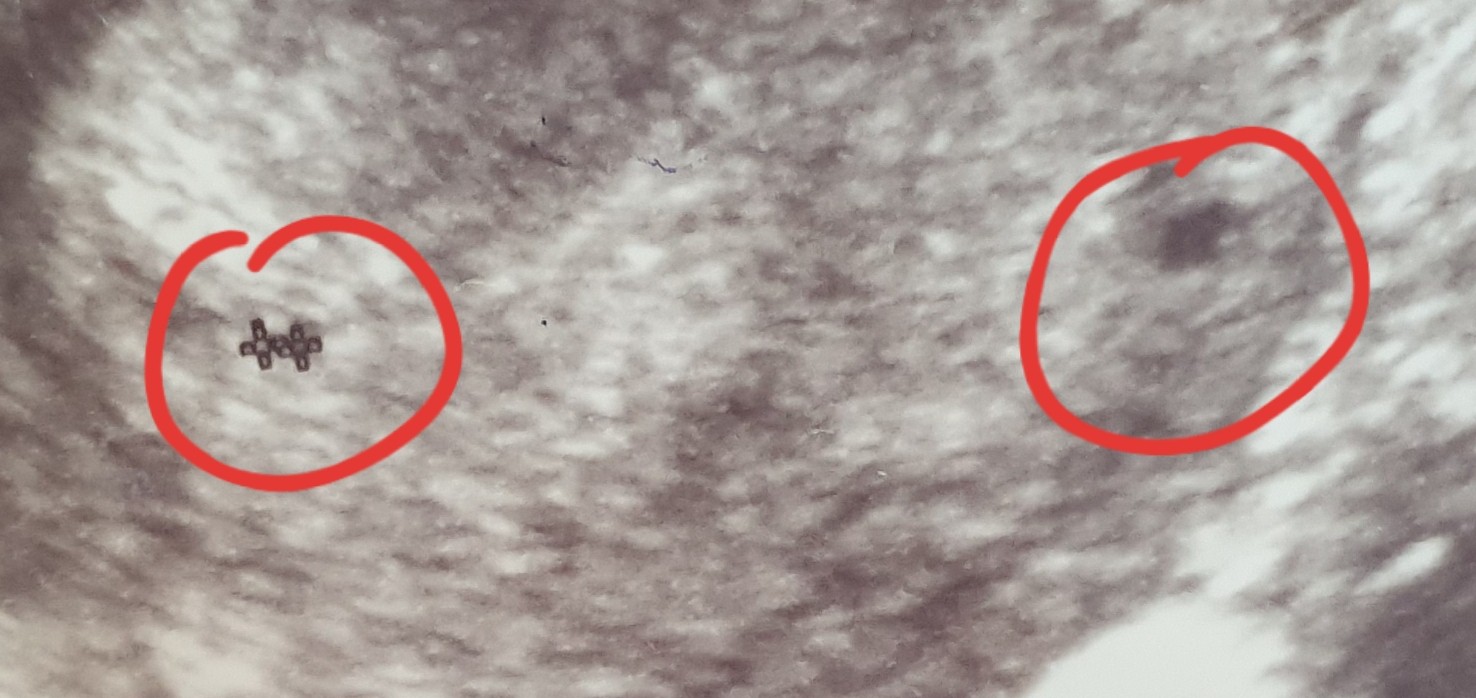

Hej mamusie. Powiedzcie mi czy tutaj jest jedenczy dwa pęcherzyki ? Z pierwszej wizyty w 5 tygodniu i drugie usgz 6 tygodnia. Ginekolog nic nie wspomniał żesą dwa za to przepisał duphaston i luteine. Czy tylko ja tam widzę dwa ?

chyba trochę za duza ta odległość. Może to jakiś krwiaczek ja tez miałam czarna plamę na USG nad pecherzykiem właściwym właśnie w 5t to lekarz mówił że nie wie co to może będę z tego krwawić. Ale minęło i na razie cisza.

nie znam się ale może to krwiaczek ? Z tego co pamietam na moim usg wyglądał podobnie do pęcherzyka 🙈 przynajmniej dla mnie 😉

Myśle ze lekarz powiedziałby Ci o drugim pęcherzyku, to dość istotne 😉